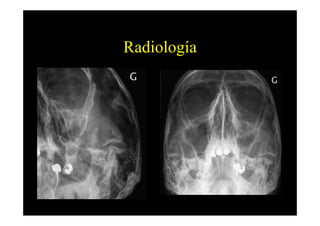

Radiología